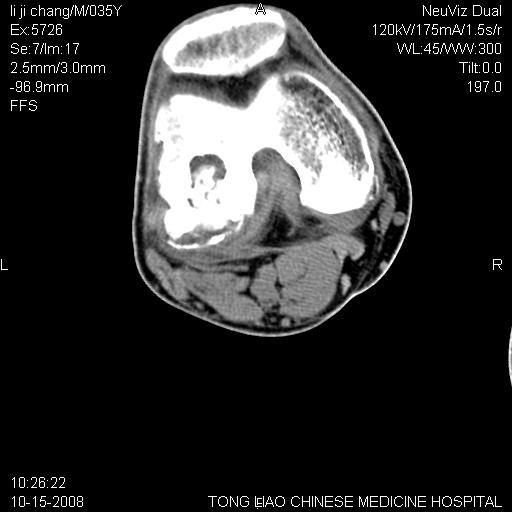

男,35岁,骨科诊断骨性关节炎。继往使用过激素,现股骨头坏死。膝关节病变,请会诊

一元论-----亦考虑为坏死

支持考虑无菌坏死

支持无菌坏死伴退行性骨关节病.

剥脱性骨软骨炎:是一种关节下软骨及软骨下骨缺血性坏死。

支持 无菌性坏死伴退行性骨关节病。